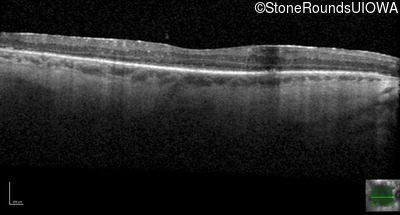

Optical Coherence Tomography - Left - 20/40 -2

Exemplar / OCT Stack

OCT Stack